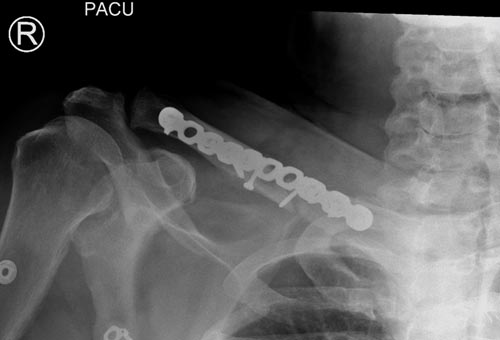

Болезненные ложные суставы надо оперировать, и здесь представлен случай

свежего болезненного ложного сустава, оперированного через 4 месяца.

Освобожден средний фрагмент и боковая компрессия лагированием, фиксация

пластиной..